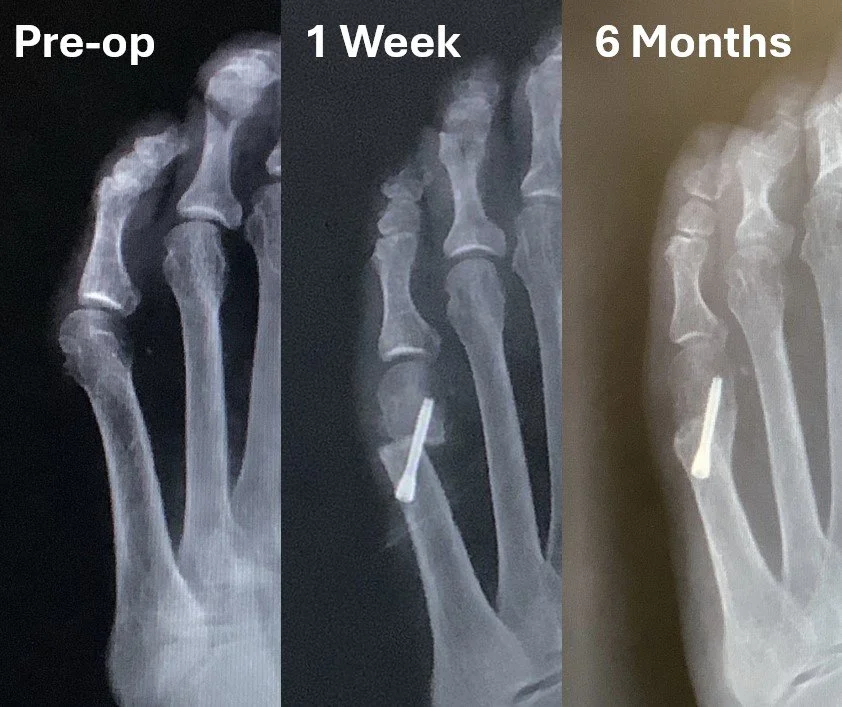

In 2024, we devised the Bunion-NET™ system to address the gaps in the minimally invasive portfolio for (Tailor’s) Bunionette correction. Our patented approach avoids the pitfalls of free-floating osteotomies and overcomes the limitations of stemmed implants with a seamless “2-stitch” approach

• Module 2: Proximal Interphalangeal Joint Fusion for Treatment of Hammertoe Deformity

• Module 3: Distal Metatarsal and Digital Osteotomies for Treatment of Mild to Moderate HAV

• Module 4: Tailor’s Bunion Correction with Metatarsal Osteotomy